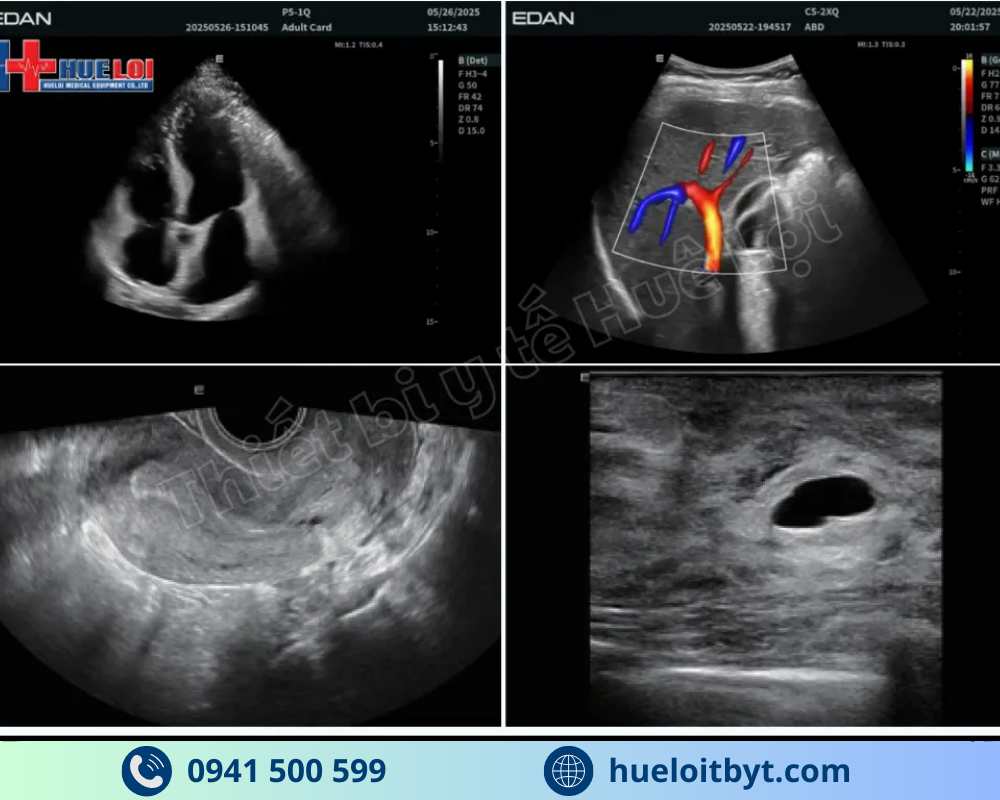

Với mức đầu tư vô cùng hợp lý, mức giá của EDAN LX85 ở thời điểm hiện tại chỉ nằm trong khoảng hơn 350 triệu đồng cho cấu hình 3 đầu dò, máy siêu âm bàn đẩy EDAN LX85 đã phá vỡ mọi quy chuẩn trong phân khúc. Điểm nổi bật nhất phải kể đến là máy sở hữu những công nghệ cao cấp vốn chỉ có trên các hệ thống đắt tiền hơn nhiều, như công nghệ đàn hồi mô Shear Wave giúp đánh giá trực quan độ cứng tổn thương, công nghệ vi mạch Micro-Flow, và đặc biệt là công nghệ e-Live giúp tái tạo khuôn mặt thai nhi một cách tự nhiên và sắc nét. Sự kết hợp giữa mức giá cực tốt và hàng loạt tính năng chuyên sâu này đã định vị EDAN LX85 là một trong những hệ thống siêu âm bàn đẩy đáng đầu tư nhất trong phân khúc dưới 500 triệu đồng hiện nay.

Công nghệ EDAN SynSight được tích hợp trong model LX85 có thể sử dụng toàn bộ thông tin dữ liệu phản hồi thu được ở mỗi vùng lớn và do đó có thể bao phủ toàn bộ trường nhìn với ít chu kỳ truyền/nhận hơn.

Thông tin phản hồi thô ban đầu được xử lý lại nhiều lần trong bộ xử lý để tối ưu chất lượng hình ảnh tạo thành.

Cùng với những ưu việt về phần cứng, máy siêu âm bàn đẩy EDAN thế hệ mới còn được tích hợp công nghệ siêu âm Micro-Flow (Microvascular Flow Imaging) là công nghệ Doppler tiên tiến, giúp phát hiện vi mạch nhỏ có dòng chảy chậm mà siêu âm Doppler truyền thống khó quan sát. Kỹ thuật này không cần dùng chất cản quang nhưng vẫn cho hình ảnh mạch máu sắc nét, hỗ trợ chẩn đoán chính xác trong siêu âm mạch, gan, thận, vú, sản phụ khoa. Với ưu điểm an toàn, độ nhạy cao và hình ảnh trực quan sắc nét, Micro-Flow Imaging ngày càng được ứng dụng rộng rãi trong siêu âm lâm sàng hiện đại.